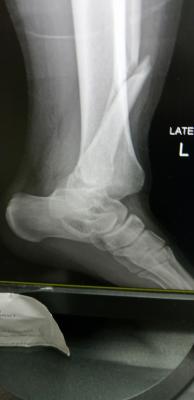

Mai scare me leg. My scan results are out. Ligament tendon all good. Just bone broken and one part dislocated. Broken part all screws. Dislocated, screwed back to strengthen.

just wait untill fractured heal...for time being slowly get range movement ankle and partially weight bearing if more than 6 week..and ostechondral injury cannot be seen in xray or ct scan..even sometimes mri also can be miss..u definitely have it as your medial malleolus fractured involving ankle joint which have cartilage over there..Mai scare me leg. My scan results are out. Ligament tendon all good. Just bone broken and one part dislocated. Broken part all screws. Dislocated, screwed back to strengthen.